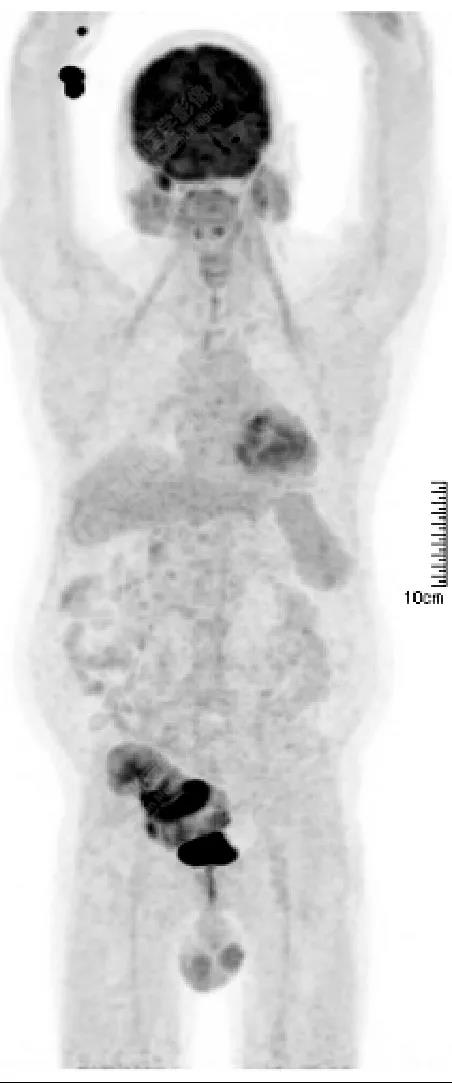

PET/CT檢查意義

發(fā)現(xiàn)全身其它部位有無結(jié)內(nèi)或結(jié)外淋巴瘤病灶。由于淋巴瘤組織多具備高代謝、大范圍無氧酵解的特性,葡萄糖需求量為正常組織細(xì)胞的20~30倍,正電子湮滅產(chǎn)生的光子信號聚集于灶區(qū),PET捕獲后可半定量分析其分布特征【4】。